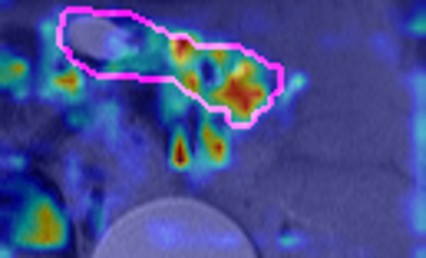

We evaluated multiple approaches for IPMN risk classification, comparing radiomics-based methods with deep learning models, and benchmarking against both established clinical guidelines and expert radiologist assessments. Our 3D DenseNet-121 model achieved superior performance in distinguishing high-risk from low-risk and no-risk IPMNs (Table 2). In a direct comparison with the Kyoto Criteria [ohtsuka2024international], our model demonstrated significantly improved diagnostic accuracy (AUC=82.371.02% vs. AUC75%, ) for T2W images. Notably, the performance improvement was most substantial in detecting high-risk lesions (sensitivity 87.8% vs. 64.1%, ), which is clinically critical for preventing missed opportunities for early intervention. To further interpret the model’s feature representation, we performed t-SNE visualization of both the input images and the hidden states from the DenseNet-121. As shown in Fig. 3, input features show limited separation across risk classes, while the learned embeddings exhibit improved clustering by risk category. This indicates that the model successfully learns discriminative representations for IPMN risk stratification.

When compared with the visual assessments of three expert radiologists, our models demonstrated superior accuracy in both no/low-risk and high-risk cases. As shown in Table 3, the DenseNet-121 model with probability fusion achieved a no/low-risk classification accuracy of 94.66% and a high-risk accuracy of 47.18%, outperforming the radiologists’ average accuracies of 93.91% and 46.01%, respectively. While this overall performance suggests that Cyst-X surpasses expert-level assessments, a more nuanced interpretation is warranted. Notably, Radiologist 2’s performance demonstrates a tendency toward high Negative Predictive Value (NPV)at the expense of sensitivity (i.e., substantially lower accuracy at just 32.39%), which risks missing malignant cases. In contrast, our model maintained a more balanced performance across risk categories, demonstrating both strong sensitivity and specificity. This balance suggests that Cyst-X is not only more accurate overall but also potentially more reliable in clinical decision-making, where both under- and over-diagnosis carry significant consequences. For visual explainability of classification results, visual saliency-based methods are often used, although most of such methods are not true explanation methods, but show mostly learned patterns in the image region in correlation to the result. For this purpose, GradCAM [selvaraju2017grad] and Information Bottleneck Attribution (IBA) [schulz2020restricting, demir2021information] based visualizations were generated (See Supplementary materials).

To interpret model predictions, we generated visual attribution maps using Grad-CAM [selvaraju2017grad] and IBA [schulz2020restricting, demir2021information]. Grad-CAM highlights spatial regions that strongly influence the model’s decision by computing gradients of the target class score with respect to feature activations. In contrast, IBA offers sharper and more focused explanations by learning a perturbation mask that minimizes mutual information between intermediate representations and predictions, thereby isolating only the most critical features for decision-making. Visualizations from both methods are provided in the Supplementary Materials.